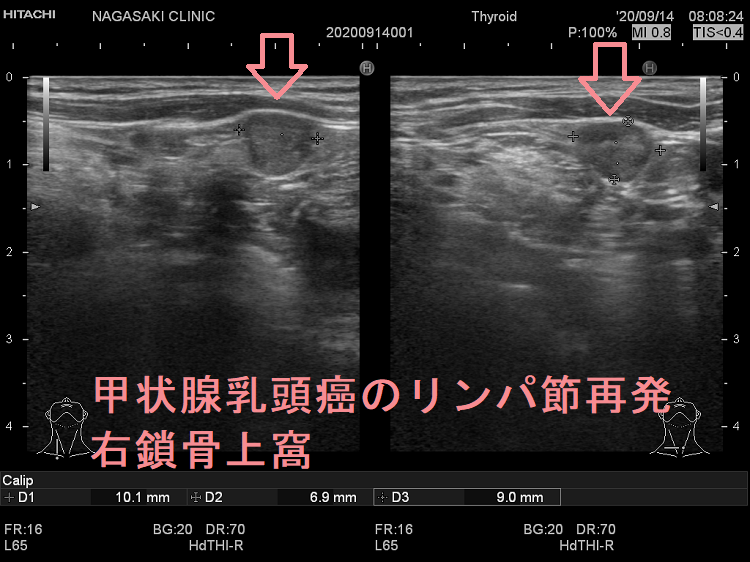

甲状腺乳頭癌鎖骨上窩リンパ節転移再発

甲状腺乳頭癌のリンパ節再発 右鎖骨上窩 超音波(エコー)画像

甲状腺乳頭癌のリンパ節再発 右鎖骨上窩 超音波(エコー)画像;いびつな形で、周囲との境界が一部不明瞭化して浸潤を疑われる。リンパ門は消失し、砂粒状石灰化を認める。

甲状腺乳頭癌のリンパ節再発 右鎖骨上窩 超音波(エコー)画像 ドプラーモード

甲状腺乳頭癌のリンパ節再発 右鎖骨上窩 ドプラーモード;内部に異常な走行の血管を認め、血流豊富。

甲状腺乳頭癌のリンパ節再発 右鎖骨上窩 超音波(エコー)画像(拡大)

甲状腺乳頭癌のリンパ節再発 右鎖骨上窩 超音波(エコー)画像(拡大);いびつな形で、周囲との境界が一部不明瞭化して浸潤を疑われる。リンパ門は消失し、砂粒状石灰化を認める。

甲状腺乳頭癌のリンパ節再発 右鎖骨上窩 超音波(エコー)画像 ドプラーモード(拡大)

甲状腺乳頭癌のリンパ節再発 右鎖骨上窩 ドプラーモード(拡大);内部に異常な走行の血管を認め、血流豊富。